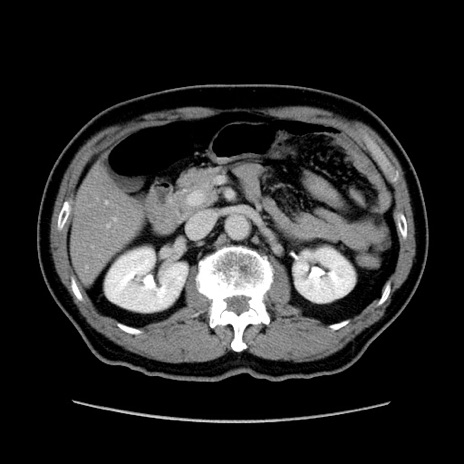

症例34(横断像)

【症例】60歳代 男性

【主訴】右鼠径部膨隆

【現病歴】1年程前より右鼠径部膨隆あり。自己にて還納可能だったため放置していた。3時間前より右鼠径部の脱出を認め、還納困難となり受診。

【既往歴】高血圧

【身体所見】右鼠径部に小児頭大の膨隆あり。弾性硬であり、用手還納は困難。左鼠径部にも膨隆を認める。脱出はなし。

【データ】WBC 15500、CRP 測定なし